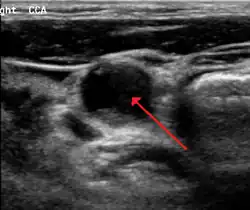

Le diagnostic est fait par échographie Doppler. Cet examen, non invasif, permet de visualiser les artères carotides, la présence ou non d'athérome et de quantifier le degré d'obstruction. Cet examen est demandé soit devant la présence d'un souffle carotidien à l'auscultation des vaisseaux du cou, soit à titre systématique chez un patient ayant déjà fait un accident vasculaire cérébral ou ayant un athérome sur une autre artère (artériopathie oblitérante des membres inférieurs ou maladie des artères coronaires.